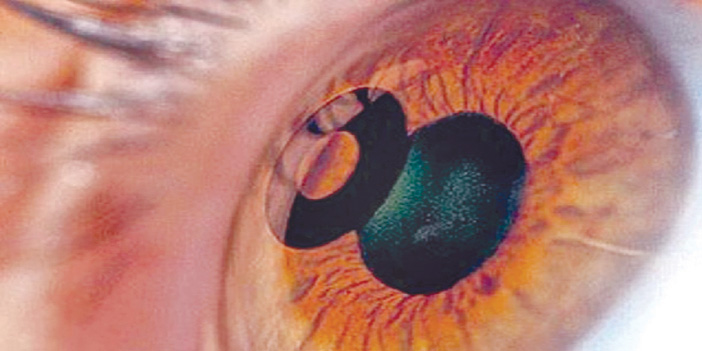

أوصت الهيئة العامة للغذاء والدواء، الأشخاص الذين أجروا زراعة عدسات بالعين من طراز كامرا (KAMRA™)، بإجراءات وقائية في حال إجراء عمليات الليزر لإزالة الماء الأزرق (الجلوكوما)، أو عمليات ليزر الفيمتوسكند (Femtosecond Laser)، أو الليزر الضوئي لشبكية العين (Retinal Laser Photocoagulation).

وأوصت الهيئة الأشخاص الذين سيجرون عمليات الليزر لإزالة الماء الأزرق بإزالة العدسات المزروعة من طراز كامرا قبل استخدام الليزر في عملية إزالة الماء الأزرق، لافتة إلى أن الشركة المصنعة أكدت أنها لم تتلق أي بلاغ عن مشكلة عند استخدام تطبيقات الليزر لإزالة الماء الأزرق، لكنها أوصت بهذا الإجراء الوقائي. ونصحت الأشخاص الذين سيجرون عمليات ليزر الفيمتوسكند (Femtosecond Laser)، بعدم استخدام تطبيق ليزر الفيمتوسكند (عمليات الليزك) لمعالجة المرضى الذين زرعت لهم تلك العدسات لوجود بلاغ عن مريض زرعت له عدسة من هذا النوع، إذ تقلصت الأبعاد المحيطية للعدسة عن حجمها الأصلي بعد استخدام ليزر الفيمتوسكند مع المريض بأشهر عدة، وظهرت أدلة على وجود حفر سطحية وتغيرات في اللون البؤري.